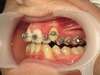

Cas n°9 traité par multi-attaches - adolescent

Ce cas d'adolescent illustre une stratégie de développement d'arcade réussie. Le patient présentait un encombrement massif et des inversions d'articulé rendant l'occlusion instable.

Le traitement a été réalisé avec des multibagues autoligaturantes, choisies pour leur capacité à générer des forces légères et continues, idéales pour l'expansion transversale. Cette approche a permis de corriger l'encombrement et les inversions d'articulé sans extractions dentaires, en remodelant simplement la forme des arcades.

Résultats clés :

• Transformation d'arcade : Passage d'une arcade étroite et encombrée à une arcade large et fonctionnelle.

• Occlusion optimale : Rétablissement d'un engrènement sain, protégeant les dents contre les usures anormales.

• Esthétique naturelle : Le sourire est élargi, harmonieux et parfaitement intégré au profil du patient.

C'est une démonstration de l'efficacité biologique de l'orthodontie moderne, qui privilégie la conservation dentaire et le respect des structures osseuses.